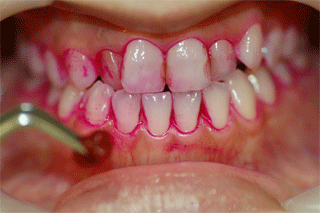

薬剤で歯に付着しているバイオフィルムを染めだし、ブラッシングの苦手箇所をチェックします。

バイオフィルムを染め出します。   ゴム製のカップなどで汚れを落とします。   着色汚れが付きにくくなります。

たばこのヤニのついた歯へのPMTCの施術例

PMTC施術前   PMTC施術後

ヤニや歯石がたくさんついています

スケーラーやジェットポリッシャーで汚れを落とします。